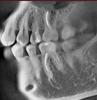

Гость Vini Vidi Vici Опубликовано 26 июля, 2008 Поделиться Опубликовано 26 июля, 2008 (изменено) Я, понимаете ли, не стоматолог. Пальцем в небо - не хочется. По поводу разъясненной верхней 6-ки - поняла, что можно жить и так, раз уж не беспокоит (пока?), а можно и переделать. Опять же мнение - перепломбировка нежелательна, если необязательна. А кто скажет, обязательна ли? Выходит, никто. А вот по поводу нижней как раз ничего не понятно, потому как повода для боли вроде как и нет, а боль есть, и не первый день. Я терпеть могу, к счастью болит в основном при воздействии, и в ухо стреляет. Жить и питаться можно. НО не хочется запустить то, что можно вылечить. Кроме того несколько вопросов озвучила выше - насчет горячей гуттаперчи при перепломбировке, и предпочтительности лечения во время или после обострения. Спасибо.А на 7 верхнем пломба давно стоит? Может быть и пульпит 27. Снимочек 26 не информативен, к сожалению. Изменено 26 июля, 2008 пользователем Vini Vidi Vici Ссылка на комментарий

zybnaya feya Опубликовано 28 июля, 2008 Поделиться Опубликовано 28 июля, 2008 Пломба стоит меньше года, пульпит подозревали, но по результатам проверки током (простите, не знаю термина) сказали - нет его. Хотя зуб реагирует на холодное. Списали на оголенную шейку. Спасибо всем! Вам перелечивать надо как нижний моляр,так и верхний. В обоих зубах каналы недопломбированы до верхушки-отсюда и все беспокойства. Горячая гуттаперча-идеальный вариант,даже не сомневайтесь. Ссылка на комментарий

Гость Vini Vidi Vici Опубликовано 30 июля, 2008 Поделиться Опубликовано 30 июля, 2008 А сначала я б депульпировала 27-там, судя по отношению пломбы к полости зуба, есть хронический пульпит. Ссылка на комментарий